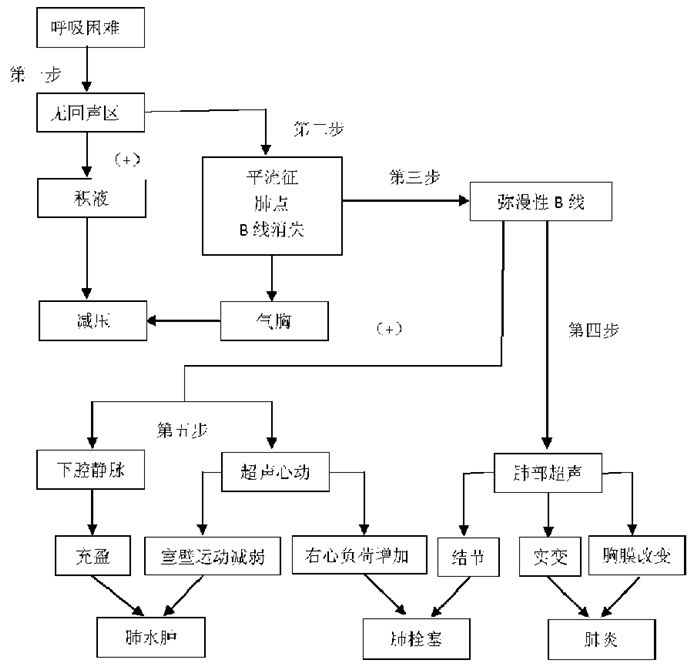

3.2.3 急性呼吸困难超声诊断步骤和流程(1)BLUE草案[21]:2008年Lichtenstein和Meziere率先针对急性呼吸衰竭患者制定了BLUE草案并发表于Chest杂志(图 30)。BLUE草案的主要影像特征为:A表现 仰卧位或半坐位的患者前胸部主要表现为A线,如存在胸膜滑动多见于慢性阻塞性肺疾病、肺栓塞、后背部肺炎;如胸膜滑动消失多见于气胸。B表现 仰卧位或半坐位的患者前胸部主要表现为B线,多见于心源性肺水肿,基本可除外慢性阻塞性肺疾病、肺栓塞及气胸。A/B表现 一侧肺为B线,另一侧为A线,通常见于肺炎。

| 图 30 肺部超声BLUE方案图 |